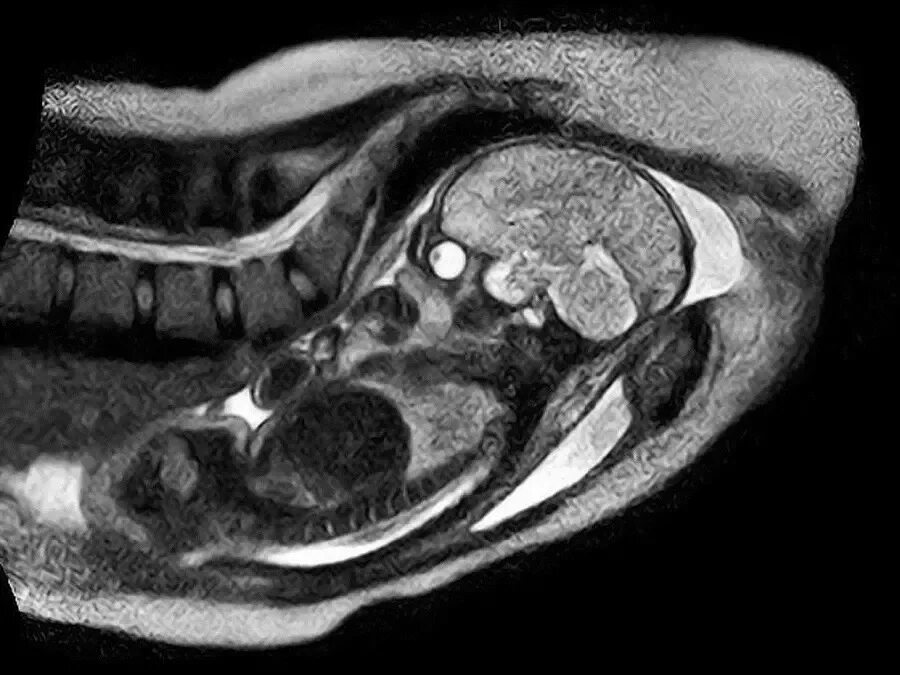

Мрт беременной